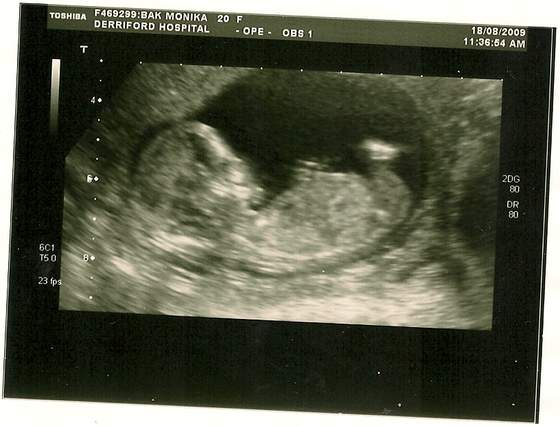

juz sie niemoge doczekac az pojdzie troszke sobie odetchne no i juz sie niemoge doczekac az bede wiedziala co mi tam za fasoleczka wyrasta odrazu tylko jak bede wiedziec zaczynam kupywac z checia bym kupila juz wszystko lozeczko wozek ubranka doslowanie wszystko ale jak to mowia z wozkiem i lozeczkiem le[piej poczekac